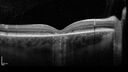

Paclitaxel induced cystoid macular edema - reversed when chemo stopped74 views74 year old retired physician About 2-3 weeks ago there was gradual vision loss in the right eye. The patient was seen by an ophthalmologist who saw macular swelling and injected vabysmo. He has been on chemotherapy (Carbiplatin and Carboxytaxol for 2 cancers - advanced prostrate diagnosed 2019 - has had brain surgery AND squamous lung cancers treated with radiation)

Medical Hx: Prostate cancer (Onset: 2018). Pulmonary and bone cancer metastatic. Brain cancer metastasized from prostate cancer.

Surgical Hx: Right frontal & Frontoparietal Craniotomy (Onset: 2024). Appendectomy. Hemorrhoidectomy. Herniorrhaphy. Prostate. Systemic Meds: Chemotherapy. Radiation. Eligard Every 3 Months 22.5 MG per 0.375 ML Prefilled Syringe. MIRALAX prn. Tums Freshers 500 MG Chewable Tablet. Vitamin D. XGEVA.

VA OD: Dcc20/125+1

VA OS: Dcc20/125-2

TP: OD:12 OS:15